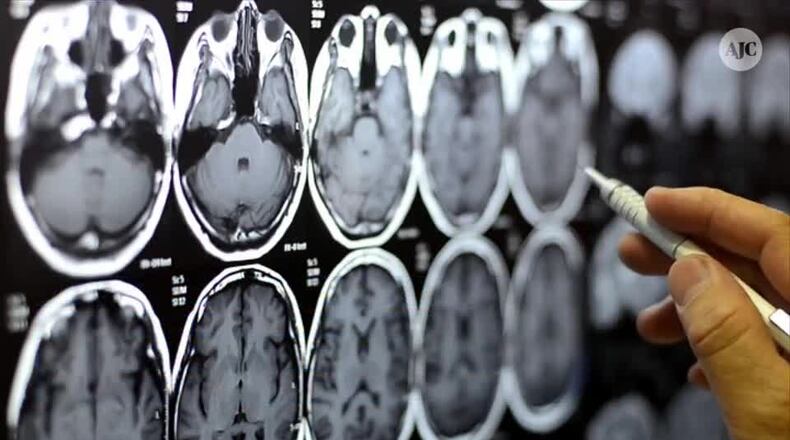

In August 2021, a preliminary but large-scale study investigating brain changes in people who had experienced COVID-19 drew a great deal of attention within the neuroscience community.

In that study, researchers relied on an existing database called the UK Biobank, which contains brain imaging data from over 45,000 people in the U.K. going back to 2014. This means – crucially – that there was baseline data and brain imaging of all of those people from before the pandemic.

The research team analyzed the brain imaging data and then brought back those who had been diagnosed with COVID-19 for additional brain scans. They compared people who had experienced COVID-19 to participants who had not, carefully matching the groups based on age, sex, baseline test date and study location, as well as common risk factors for disease, such as health variables and socioeconomic status.

The team found marked differences in gray matter – which is made up of the cell bodies of neurons that process information in the brain – between those who had been infected with COVID-19 and those who had not. Specifically, the thickness of the gray matter tissue in brain regions known as the frontal and temporal lobes was reduced in the COVID-19 group, differing from the typical patterns seen in the group that hadn’t experienced COVID-19.

In the general population, it is normal to see some change in gray matter volume or thickness over time as people age, but the changes were larger than normal in those who had been infected with COVID-19.

Interestingly, when the researchers separated the individuals who had severe enough illness to require hospitalization, the results were the same as for those who had experienced milder COVID-19. That is, people who had been infected with COVID-19 showed a loss of brain volume even when the disease was not severe enough to require hospitalization.

Finally, researchers also investigated changes in performance on cognitive tasks and found that those who had contracted COVID-19 were slower in processing information, relative to those who had not.